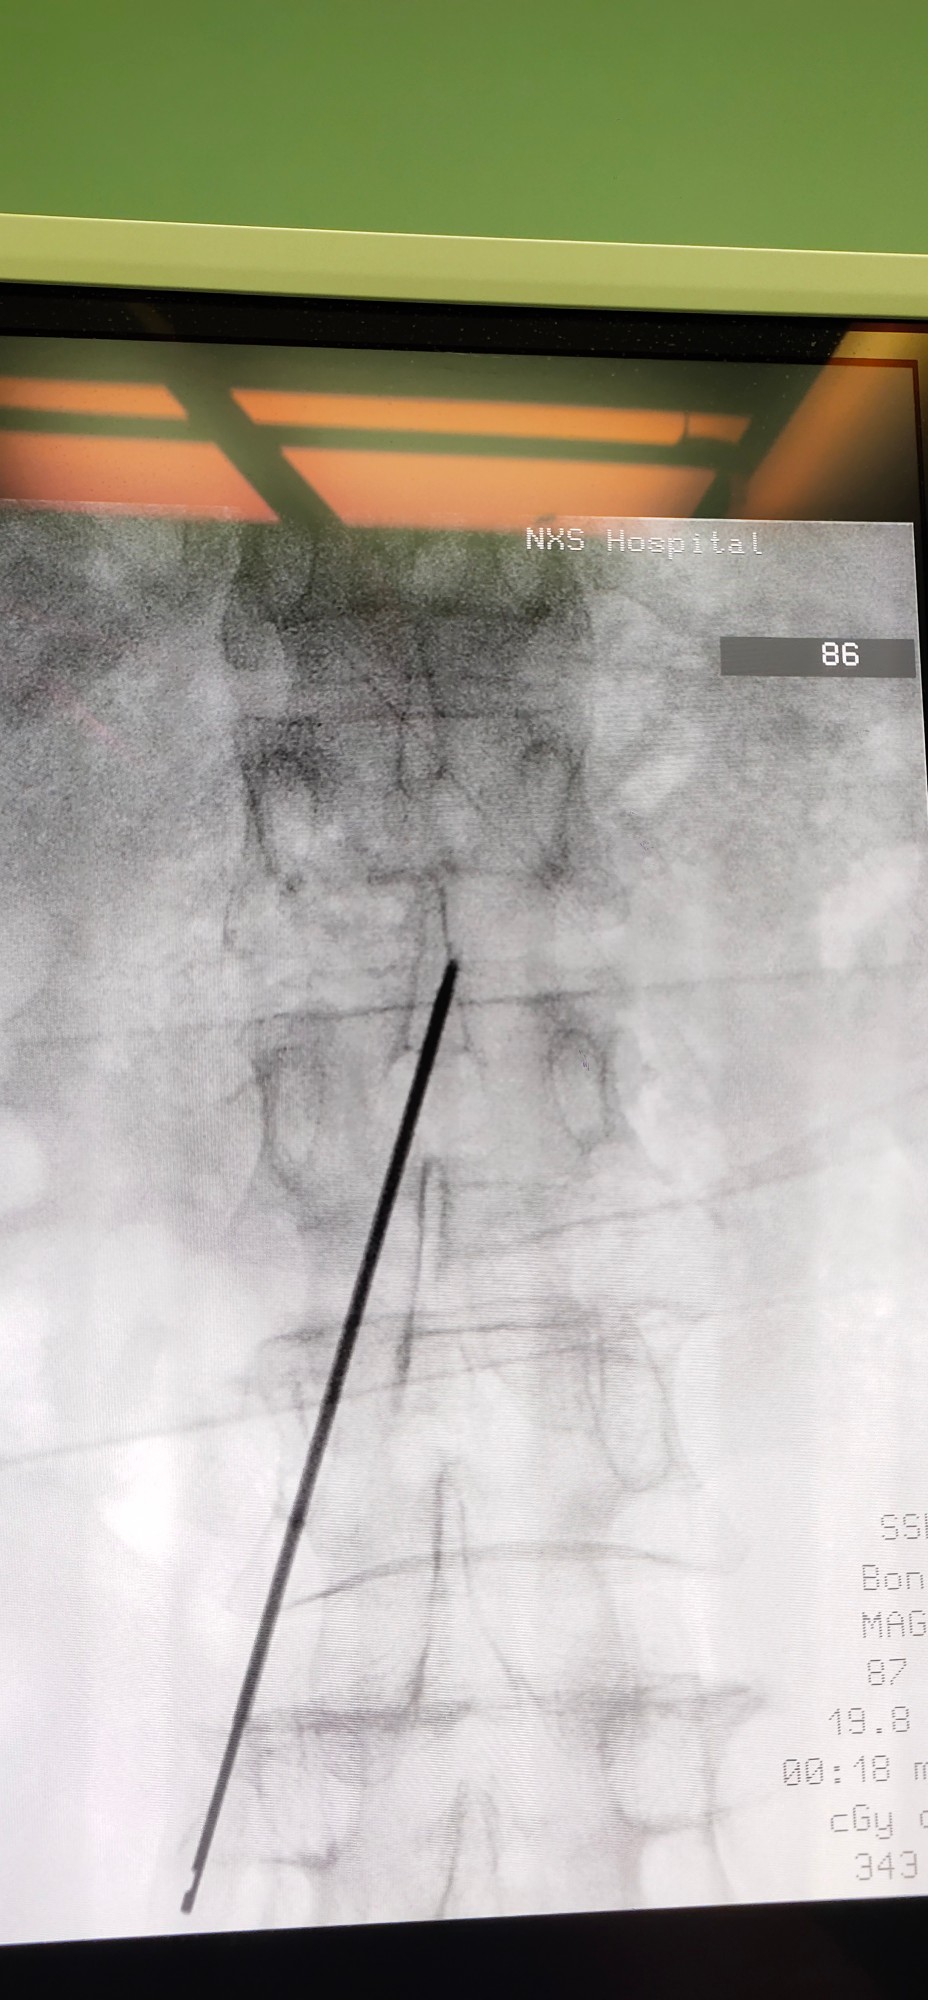

经过术前腰穿测试和充足的准备后,田文海主任团队为该患者顺利进行了全植入式鞘内药物输注系统术,患者由原来的口服盐酸羟考酮缓释片180mg/24小时,转变成每日鞘内输注0.15mg的剂量,疼痛控制效果跟口服药物相比,有了明显的提高。植入鞘内泵后,患者左侧额颞面部疼痛得到有效控制,VAS评分稳定到0~2分,日常生活质量得到极大的改善,患者再也不会因为疼痛难忍而睡不着觉了。

田文海介绍,对于难治性疼痛而言,鞘内药物灌注疗法是目前的趋势,这种疗法通过体内植入一个储存药物的泵,将镇痛药(盐酸、吗啡)直接输注到人体蛛网膜下腔的脑脊液中,使脊髓灰质相应的靶点与阿片类受体结合,阻断疼痛信号上传到大脑皮质,从而达到更快速、有效、持续性的止痛效果。相对于全身使用阿片类药物,鞘内给药更为安全,并发症和死亡率更低,所需剂量仅仅是口服药的1/300、静脉注射的1/100,极大地减轻了全身性过量药物给人体所造成的副作用。该项技术的临床应用给所有的难治性疼痛患者包括癌性疼痛,带来了远离疼痛、获得高质量生活的希望。